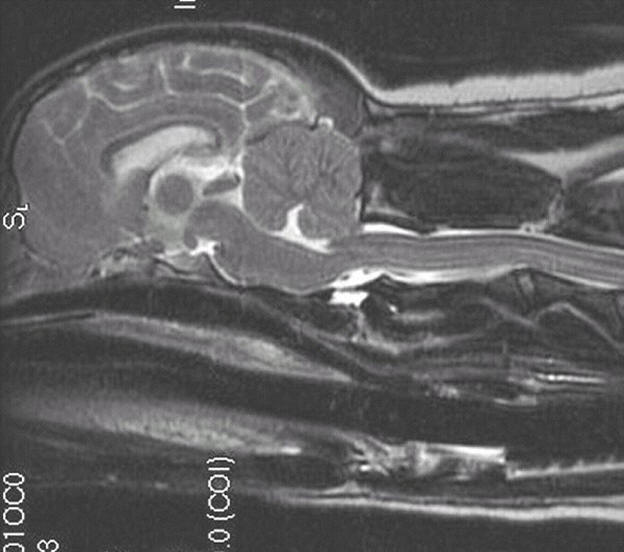

1.5 years old

Symptoms: Scoliosis, head tilt,

scratching, right front paw/leg very weak

Mild malformation, mild

squashing/pinching of cerebellum

Herniation of cerebellum

Medulla kinked/squashed

Syrinx beginning near brain (before C2)

and continuing all the way back

Mild hydrocephalus